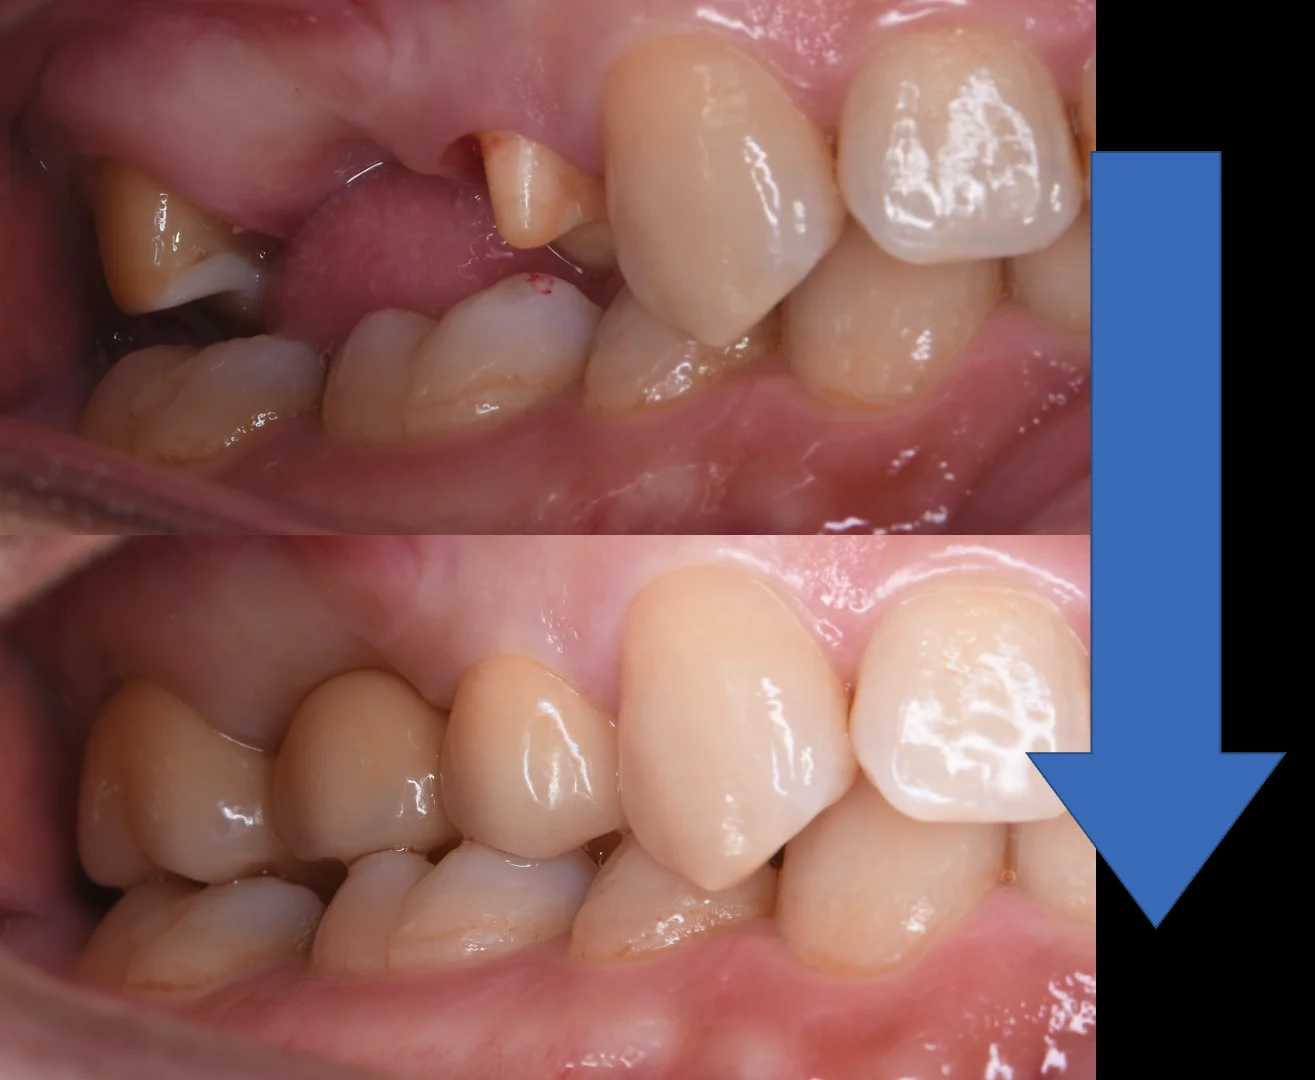

そして術前と術後の比較がこちらです。

セラミックのブリッジ|坂寄歯科医院(取手市藤代) - 画像3

今回の症例でもそうですが、私は大体形作りと型取り・仮歯作成を1日に同時で行うことが多いです。

しかし、場合によっては仮歯の作成と型取りを別日に分けることもあります。

その際には来院回数が1回増えてしまいますが、適合のいい被せ物を入れるためですので、ご了承いただければ幸いです。